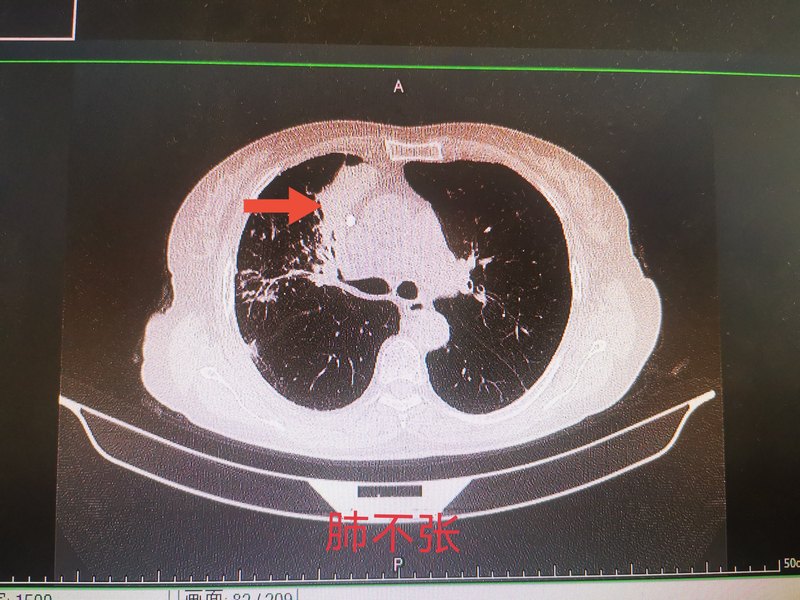

繼發(fā)性肺結(jié)核從病理和X線形態(tài)特點上有滲出性肺結(jié)核、增生性肺結(jié)核、纖維干酪性肺結(jié)核、干酪性肺炎、空洞性肺結(jié)核、結(jié)核球(瘤)、慢性纖維空洞性肺結(jié)核等的區(qū)分。繼發(fā)性肺結(jié)核病變形態(tài)很少是單一性的,常是多種形態(tài)并存,以某一種為主。由于強(qiáng)力高效化療的推行,病理和X線形態(tài)上區(qū)分對治療意義不大,但對鑒別診斷仍有一定幫助。繼發(fā)性肺結(jié)核易形成干酪樣壞死和空洞,排菌者較多,在流行病學(xué)上更具重要性。多數(shù)病人有發(fā)熱、咳嗽、咳痰等癥狀,少數(shù)病人可無癥狀或僅有輕微癥狀,健康檢查時發(fā)現(xiàn)。(1)起病緩慢,咳嗽,咳痰,可伴咯血、胸痛、呼吸困難等癥狀。(2)發(fā)熱(常午后低熱),干酪性肺炎者,起病常急劇,初起可高熱,以后呈弛張熱伴嚴(yán)重結(jié)核中毒癥狀,可伴盜汗、乏力、食欲降低、體重減輕、月經(jīng)失調(diào)。(3)少數(shù)患者可有結(jié)核變態(tài)反應(yīng)引起的過敏表現(xiàn):結(jié)節(jié)性紅斑、泡疹性結(jié)膜炎和結(jié)核風(fēng)濕癥等。(4)糖尿病、塵肺、胃大部切除術(shù)、慢性腎功能衰竭、器官移植和骨髓移植術(shù)后、長期使用皮質(zhì)類固醇或免疫抑制劑治療的患者應(yīng)警惕是否合并肺結(jié)核,HIV感染者肺結(jié)核發(fā)病率高。體征:長期慢性消耗可呈營養(yǎng)不良、貧血;胸部陽性體征因肺部病變大小、程度、有無并發(fā)癥而差異很大。肺部病變較廣泛時可有相應(yīng)體征,如局部叩濁,病變局部可聞及支氣管肺泡呼吸音。大面積浸潤病變、干酪性肺炎、肺不張時可聞管狀呼吸音。局限性的中小水泡音常提示有空洞或并發(fā)支擴(kuò),空甕性呼吸音提示有巨大空洞。

76歲老人咳嗽、氣短,竟然不是老慢支? 76歲楊阿姨近1個月來出現(xiàn)咳嗽,氣短,家人考慮年齡大了,肯定是老慢支,也不是什么大病,就沒有到醫(yī)院檢查。結(jié)果氣短的越來越厲害,晚上整夜的咳嗽,嚴(yán)重影響了休息,這才在女兒的陪同下來到了醫(yī)院。 拍完片子后咳嗽,氣短的原因終于找到了,原來是支氣管結(jié)核和肺結(jié)核。 隨著年齡增大,老年人抵抗力下降,容易出現(xiàn)結(jié)核桿菌的感染,一旦出院咳嗽、咳痰2周以上,一定要排查是否有結(jié)核菌感染,如果出現(xiàn)盜汗、乏力、體重減輕,那感染的可能性更大。